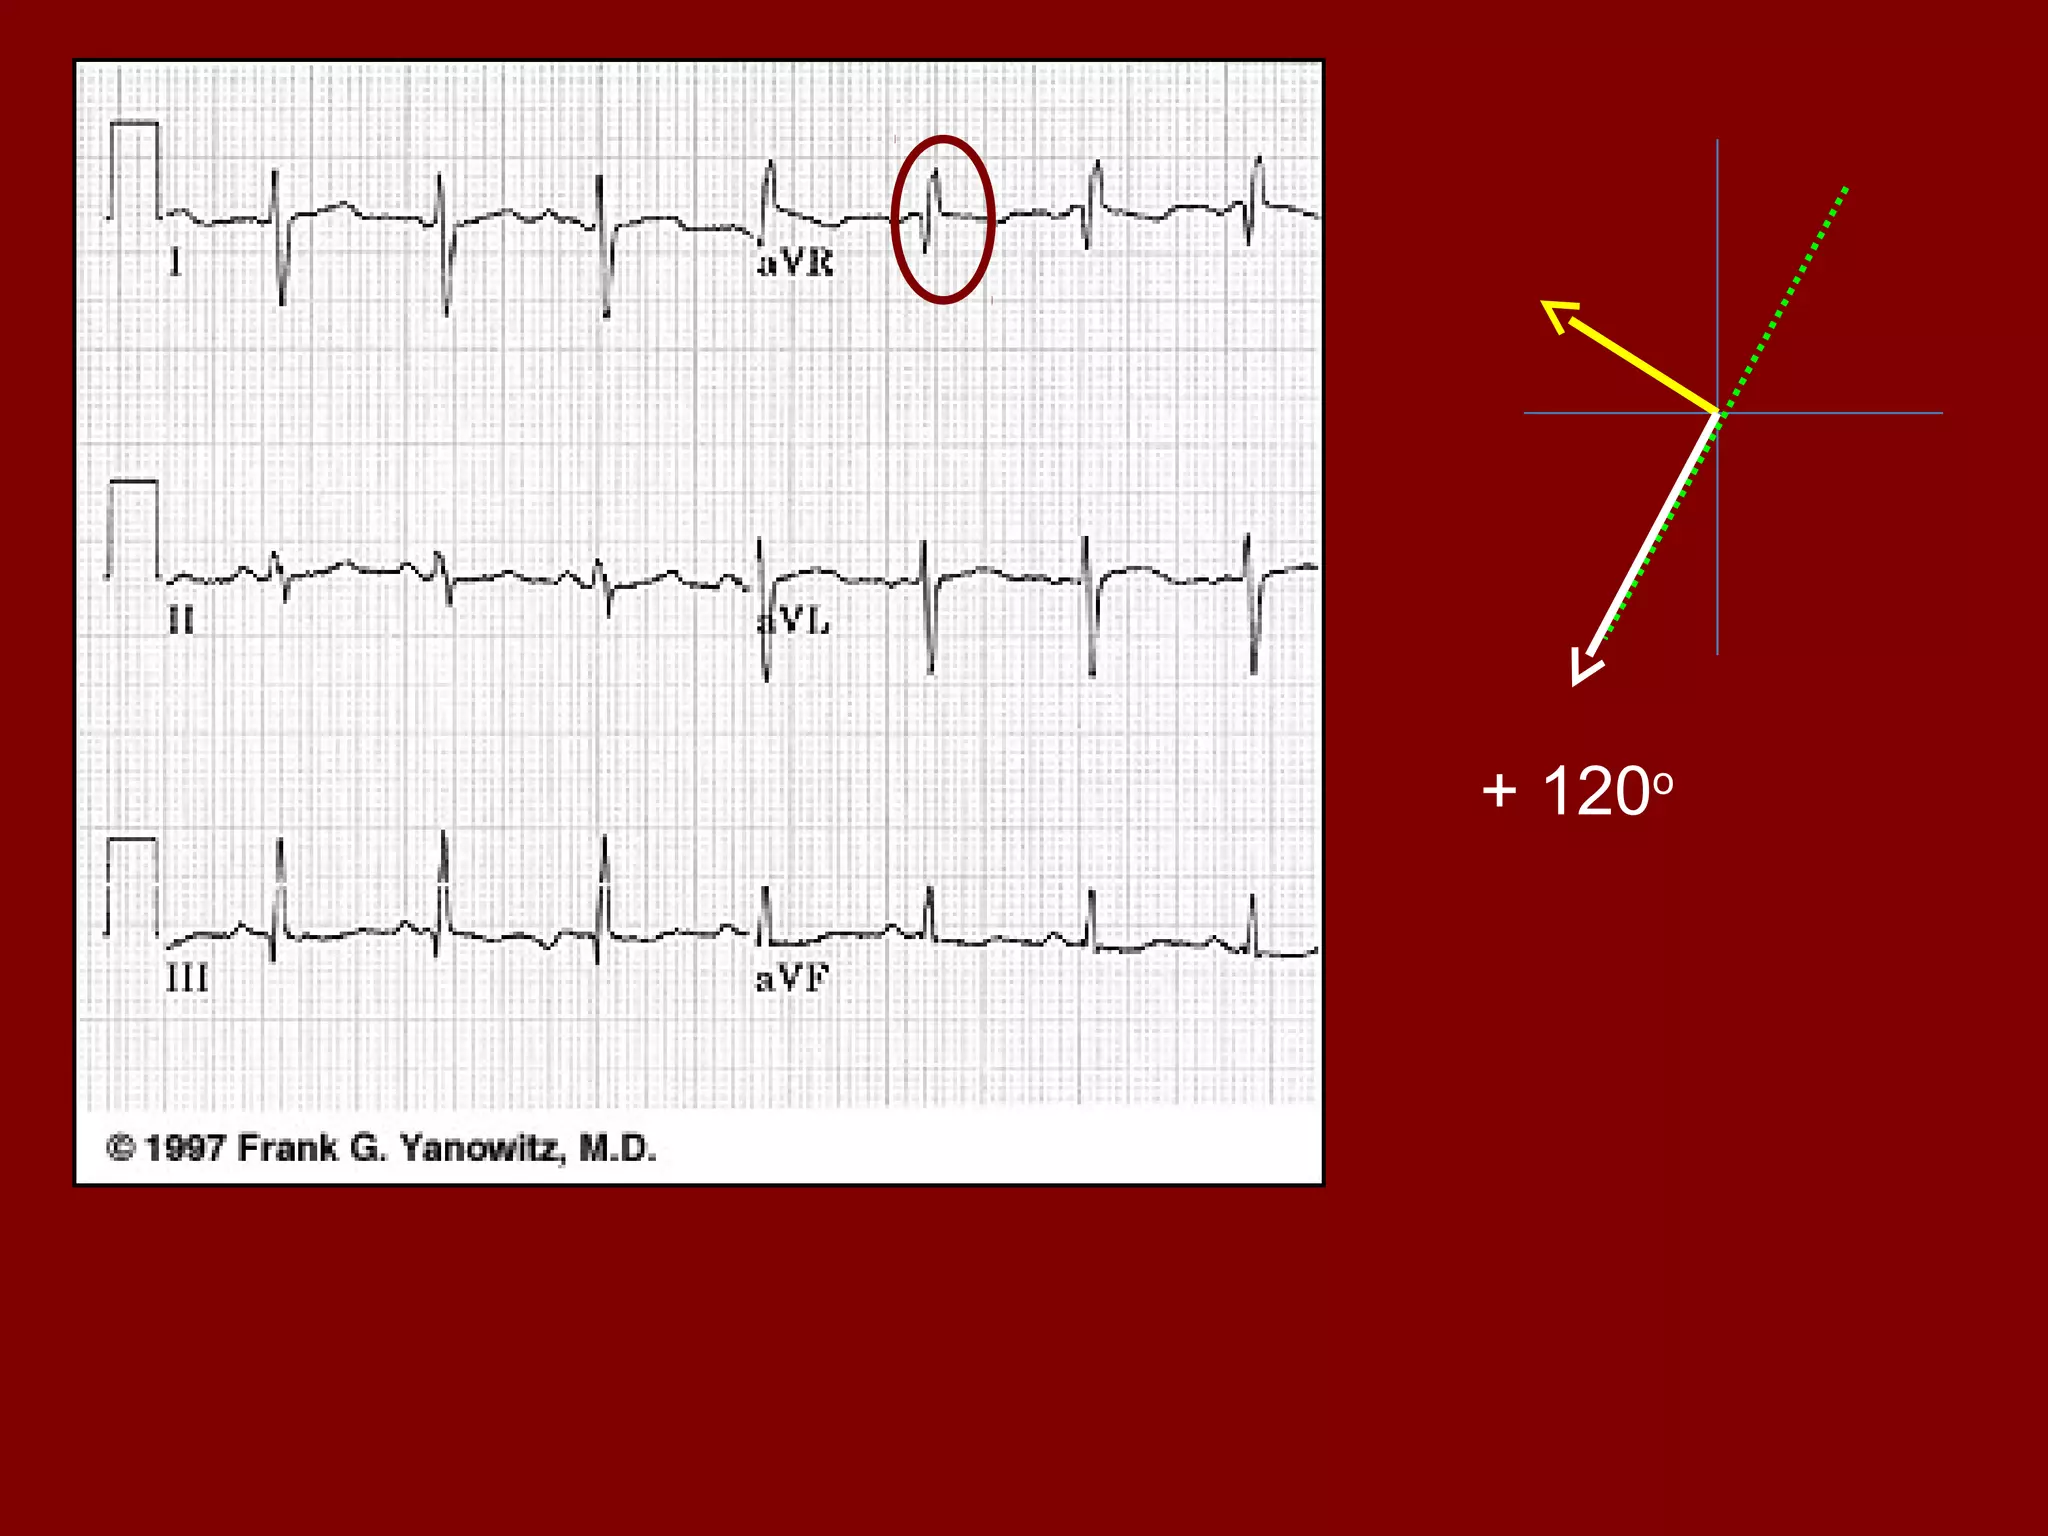

Electrical axis • Normalaxis is between -30o & +90o • Determined by the QRS axis • It is the general direction in the frontal plane towards which the QRS is predominantly pointing I III IIaVF aVR aVL-30o 0o +60o +90o +120o -150o Left axis deviation Right axis deviation

• Important toremember in QRS axis calculation 1. The mean QRS axis points midway between any two leads that shows tall R waves of equal height 2. The mean QRS is oriented at right angles to any lead showing a biphasic complex and towards the lead which has a tall R wave Generally use Lead I and aVF Electrical axis